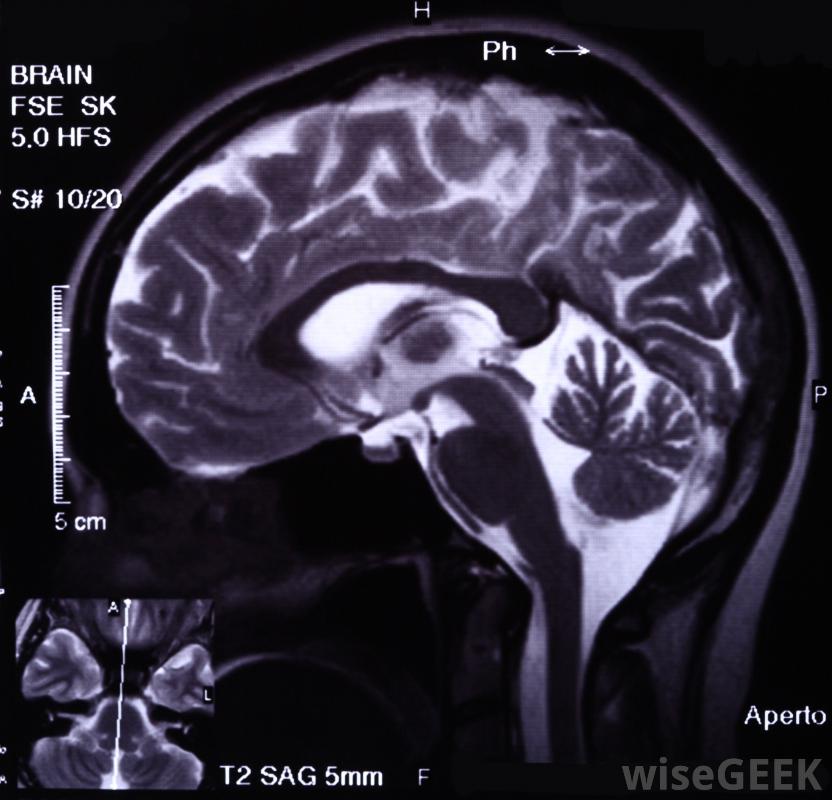

介入神经病学专家可以使用MRI技术诊断患者的病情在介入神经学中,医生使用医学影像设备清楚地显示出感兴趣的区域,以便他或她可以进行手术。例如,在栓塞治疗过程中,为了减少介入治疗的时间和风险,医生可以设计一种介入治疗的介入治疗方法神经科医生包括:中风、血管畸形、动静脉畸形、血管痉挛、某些类型的肿瘤和动脉瘤

神经影像学可用于诊断大脑和中枢神经系统的许多问题,以及辅助治疗这一领域的专家可以在工作过程中使用各种医学成像设备。他们可以拍摄静止图像和视频,根据他们的需要和病人的情况。除了使用医学影像来指导手术外,介入神经科医生还可以利用影像进行诊断,检查头部、颈部和脊椎是否有异常迹象,这可以解释为什么病人会出现神经症状神经学是一门专门研究大脑和人类神经系统其他部分状况的医学专业,也称为神经介入手术或介入治疗神经放射学。该领域的合格专家数量有限,需要介入神经科医生服务的患者可能需要去大城市接受治疗,因为大城市往往提供更多的选择,包括在大学附属医院的治疗,这些医院可能提供一些最新的医学技术,包括介入神经学。